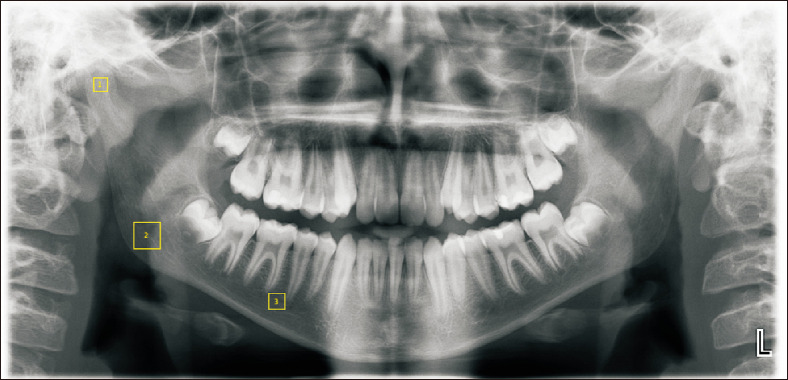

Objective: This study aimed to examine the effects of unilateral crossbite on the structure of the mandibular bone by using fractal analysis.

Methods: This study was conducted using panoramic films obtained retrospectively from 45 individuals with crossbite and 45 individuals with normal occlusion (NO). Fractal measurements were performed on the condyle, corpus, and angulus on both left and right sides of the panoramic films. The films were divided into three groups: cross-side (Cs), normal-side (Ns), and NO. The Cs group was further analyzed on the basis of the number of teeth in the crossbite. Data were analyzed using the non-parametric Kruskal-Wallis test and post-hoc Dunnett's T3 multiple-comparison test. Statistical significance was set at P < 0.05.

Results: The mean condylar fractal dimension (FD) showed no significant difference between the groups (P > 0.05). The mean angulus FD in the Cs group was significantly higher than that in the NO group (P = 0.006). Similarly, the mean corpus FD in the NO group was significantly lower than those in the Cs and Ns groups (P = 0.003). In the Cs group, comparisons based on the number of teeth in the crossbite showed no significant differences among the condyle, angulus, or corpus regions.

Conclusions: Fractal analysis may be an effective approach for detecting variations in mandibular trabecular patterns associated with unilateral crossbites. In cases of unilateral crossbite, the trabecular structure was affected in the angulus and corpus regions.